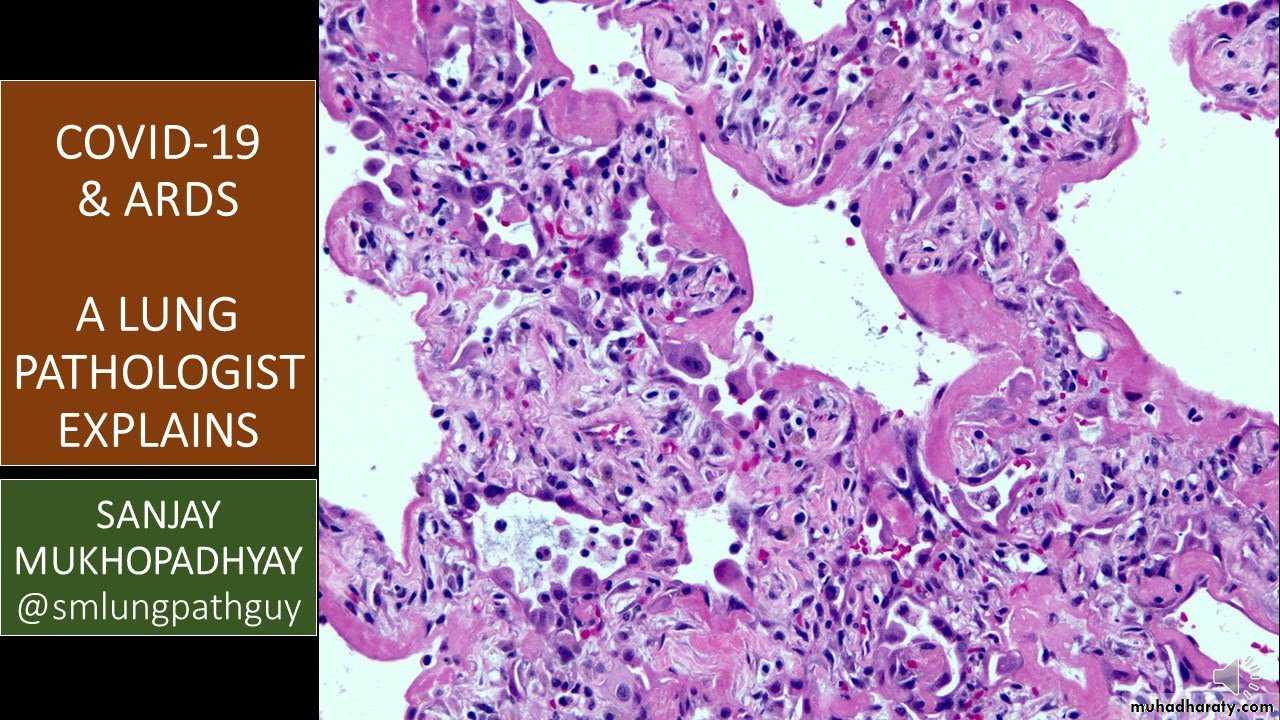

They exhibit congestion, interstitial and intra-alveolar edema, inflammation, and fibrin deposition. The alveolar walls become lined with waxy hyaline membranes . Alveolar hyaline membranes consist of fibrin-rich edema fluid mixed with the cytoplasmic and lipid remnants of necrotic epithelial cells, resolution is unusual; more commonly, there is organization of the fibrin exudate, with resultant intra-alveolar fibrosis.

(A) Diffuse alveolar damage in the acute phase. Some alveoli are collapsed,while others are distended; many are lined by bright pink hyaline membranes

(arrow). (B) The healing stage is marked by resorption of hyaline membranes

and thickening of alveolar septa by inflammatory cells, fibroblasts, and collagen.

Numerous reactive type II pneumocytes also are seen at this stage

(arrows), associated with regeneration and repair.

The important pathological changes seen in patent died from COVID 19 infection Interstitial inflammation, diffuse alveolar damage, and necrotizing bronchitis/bronchiolitis are general histopathological findings of lung in respiratory viral infections, diffuse alveolar damage is the most commonly observed finding with respiratory virus infections both in acute and late (organizing) stages, The characteristic features of acute diffuse alveolar damage are intra-alveolar edema. Fibrin deposition and formation of hyaline membranes lining the alveolar walls follow. Late diffuse alveolar damage stages are Type II pneumocyte proliferation, granulation tissue formation, followed by collagen deposition.

Histologic changes from case 1. (A) Proteinaceous exudates in alveolar spaces, with granules; (B) scattered large protein globules (arrows); (C) intra-alveolar fibrin with early organization, mononuclear inflammatory cells, and multinucleated giant cells; (D) hyperplastic pneumocytes, some with suspected viral inclusions (arrow).

(A) Evident proteinaceous and fibrin exudate; (B) diffuse expansion of alveolar walls and septa owing to fibroblastic proliferations and type II pneumocyte hyperplasia, consistent with early diffuse alveolar damage pattern; (C) plugs of proliferating fibroblasts or “fibroblast balls” in the interstitium (arrow); (D) abundant macrophages infiltrating airspaces and type II pneumocyte hyperplasia.